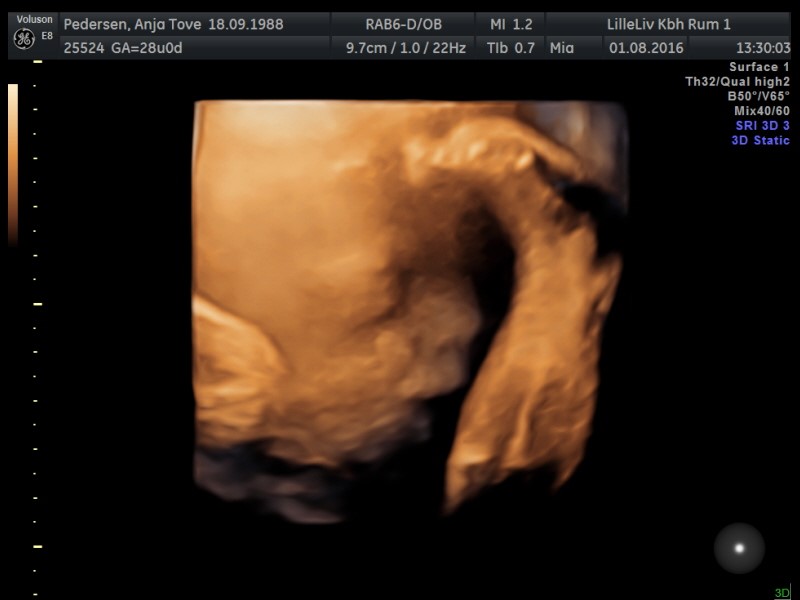

Vi har valgt gaver fra til hinanden og i stedet tog vi til 3D/4D skanning for at se til prinsessen

Hvilken fantastisk oplevelse! Hun startede med at have foden i hovedet, men hun var dog lidt sød og lagde sig anerledes så vi kunne se hendes smukke ansigt

Billeder af maven bliver ikke denne gang, men af prinsessen i 3D

Vedhæftede fotos (klik for at se i fuld størrelse)